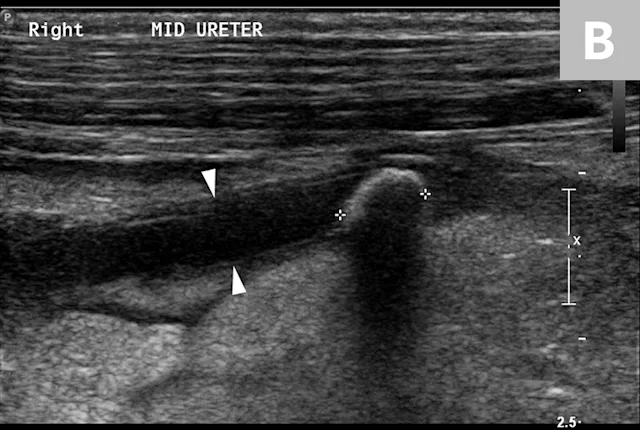

Ureteral calculi are a common cause of ureteral obstruction; localization of ureteral calculi is imperative prior to choosing appropriate management. While ureteral calculi have been reported as the most common cause of ureteral obstructions, other causes such as iatrogenic ligation, blood clots, tumor, strictures (congenital and acquired), solidified blood stones, and a circumcaval ureter have been reported.4-7

The obstruction can be located at any point of the ureter and can vary in severity. Normal ureters are typically not seen on ultrasonography due to their small size. The easiest way to locate a dilated ureter is to trace the ureter from the renal pelvis. In most cases, the ureter is dilated proximal to the site of an obstruction and tapers to a more normal appearance distal to the site of obstruction. Imaging can also reveal retroperitoneal effusion which can result from ureteritis and possible urine leakage.

Clinical signs associated with ureteral calculi may range from chronic non-specific signs to acute or chronic renal failure. The presence of hydronephrosis can be highly suggestive of a ureteral obstruction (Figure 6).